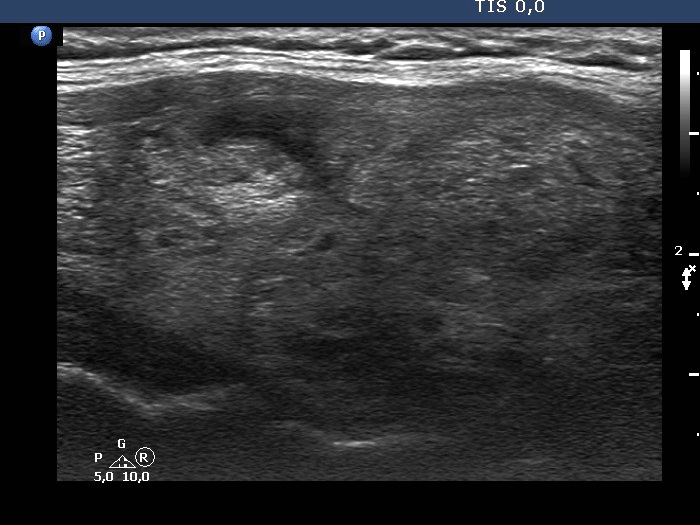

Ultrasonography. The thyroid was composed of numerous discrete lesions of various echogenicities. There was a partly cystic nodule in the upper-ventral part of the right lobe. The left lobe contained several cystic areas having comet tail artifacts.

Comment. The distinction between a cystic nodule and a cystic area is based on the size and the sum of the lesion and on the internal content. If the latter suggest a pure cyst in multiple lesions smaller than 1 cm in maximal diameter, than the lesions are very likely not true nodules but dilated macrofollicles.